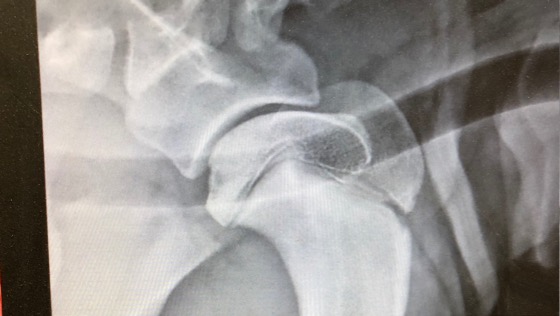

Przyjechała do nas aż z Bośni , była szczęśliwym psiakiem, niestety juz w pierwszych tygodniach pobytu jej zdrowie zaczęło się komplikować. Pierwsze rtg i problemy ze stawami biodrowymi, zabieg zespolenia juz sporo nas kosztował. Cojka była pozbawiona ruchu przez 2 tyg. Była bardzo smutna i przybita. Każdy by był. Kiedy już wszystko wróciło do normy i poczynała swoje pierwsze podrygi zaniepokoiła nas kulawizna na przednia łape. Diagnoza :OCD- osteochondroZa, niestety zajęte obie łapy, plis niepokojace zmiany w dolnuch częściach łapek. Cojka jest od 2 tyg na lekach przeciwbòlowych, niestety nie moze biegać , skakać . Jest smuna , nieszczęśliwa bo bola ja bardzo łapki.